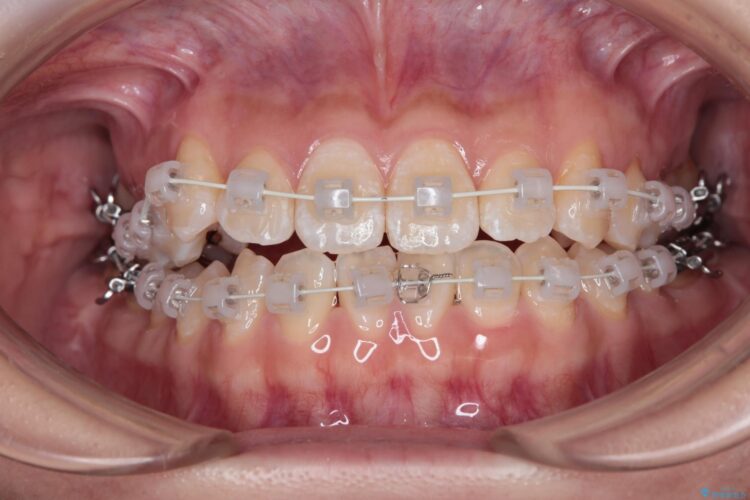

右側の八重歯の部分は噛み合わせをよくするためにゴム掛けを行いました。

また、セラミックと銀歯の部分は装置が脱離してしまうので、矯正用の仮歯に変えて治療を行いました。